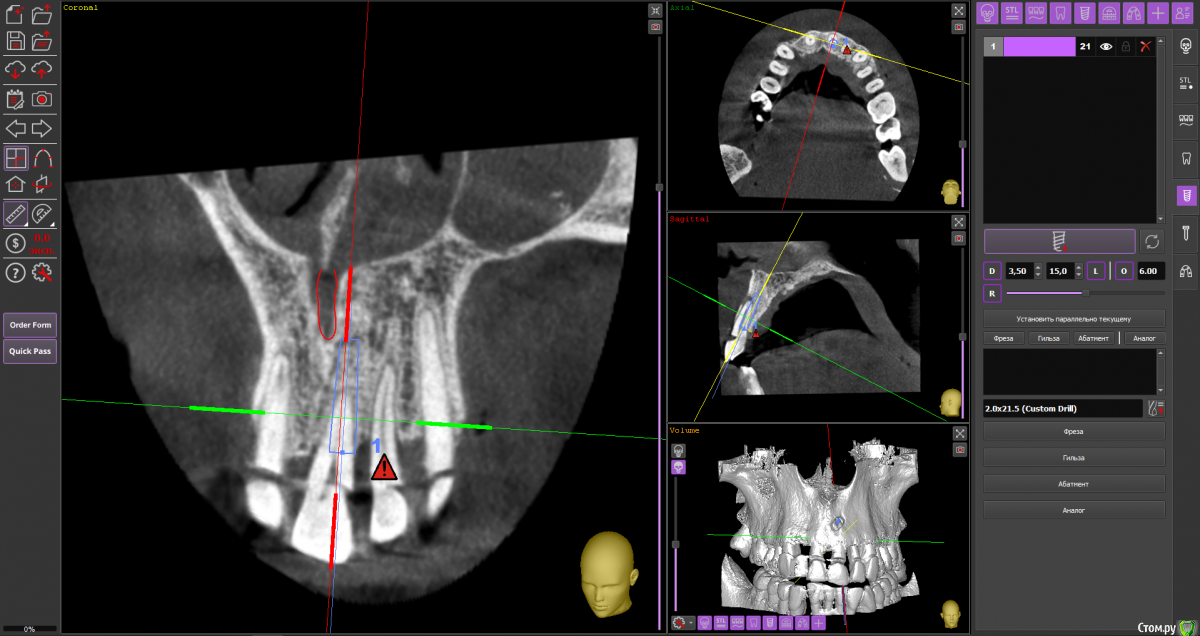

almaz7888 Опубликовано 28 января, 2021 Поделиться Опубликовано 28 января, 2021 Доброе утро коллеги! Планирую одномоментную имплантацию в область 2.1 зуба ( AnyRidge 3.5*11.5). В области апекса костный дефект. Думаю заполнить ксенографтом и перекрыть резорбируемой мембраной 1.5*2.0. Думал насчет спейсера Стоит ли такой имплант сразу нагрузить? или же лучше сделать адгезивный мост. Ссылка на комментарий

alboard Опубликовано 28 января, 2021 Поделиться Опубликовано 28 января, 2021 В том положении, которое на кт, сомневаюсь, что получите торк и сможете нагрузить... Взять подлиннее, поставить небнее и заглубить еще 4 Ссылка на комментарий

Irouil Опубликовано 28 января, 2021 Поделиться Опубликовано 28 января, 2021 Винт длиннее, выход в резцовый, стт, временная коронка 1 Ссылка на комментарий

almaz7888 Опубликовано 28 января, 2021 Автор Поделиться Опубликовано 28 января, 2021 Спасибо, тогда возьму 3.5*15. А резцовый нерв коагулирую и заполняю канал графтом или же можно без прижигания обойтись? Ссылка на комментарий